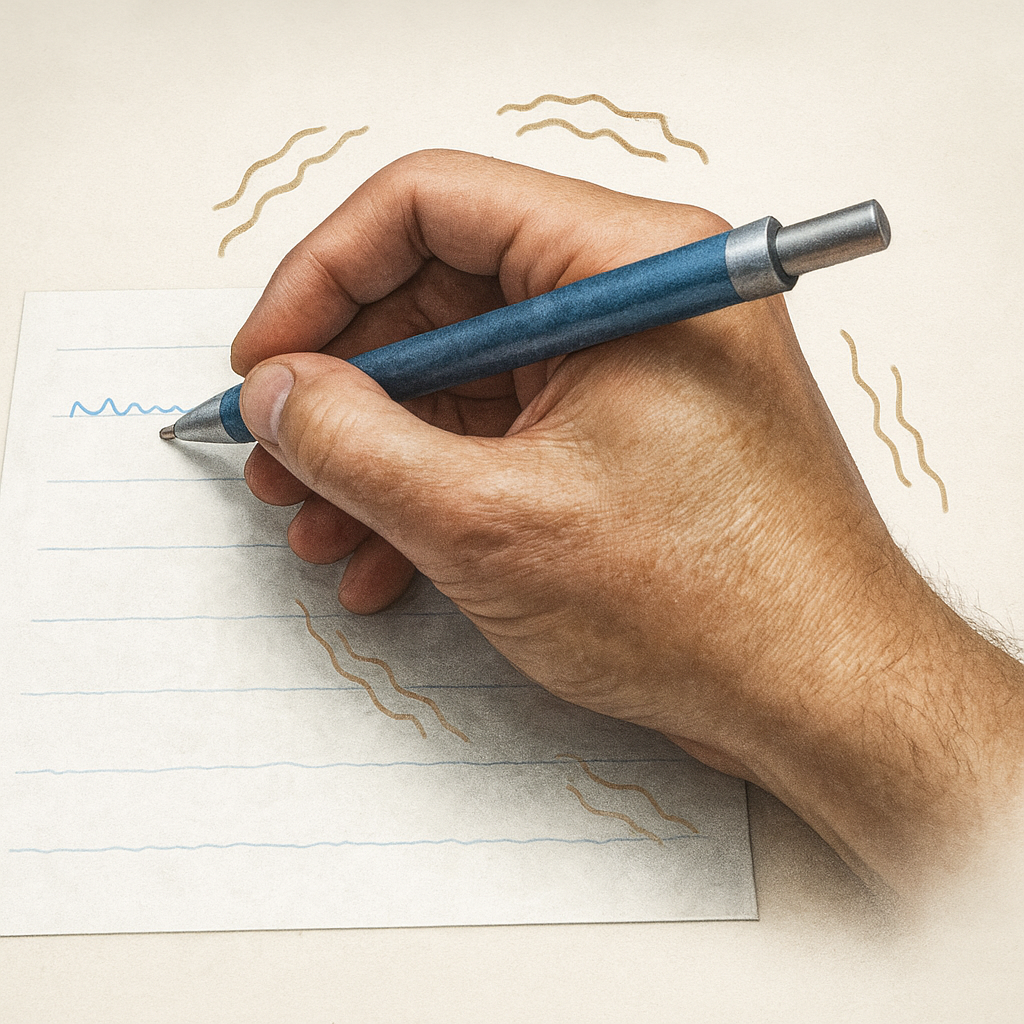

Algumas pessoas notam o tremor quando estão em repouso. Outras, quando estão tentando fazer algo com as mãos, como segurar um copo ou escrever.

Em casos mais leves, o tremor pode nem ser percebido. Mas quando fica mais intenso, pode atrapalhar tarefas simples do dia a dia, como se vestir, comer ou escrever.

- Lentidão para iniciar ou completar movimentos

- Escrita pequena e apertada

O tremor essencial é o tipo mais comum de tremor que existe. Ele costuma afetar as mãos, mas também pode atingir a cabeça, a voz ou outras partes do corpo.

Diferente do tremor do Parkinson, que aparece quando a pessoa está parada, o tremor essencial surge quando você está fazendo algum movimento, como:

- Beber água

- Escrever

- Comer com talheres

- Passar maquiagem ou fazer a barba

Geralmente, ele começa de forma leve e vai piorando aos poucos com o tempo. Em muitos casos, a pessoa convive bem com ele, mas quando começa a atrapalhar tarefas do dia a dia, é importante procurar um neurologista.